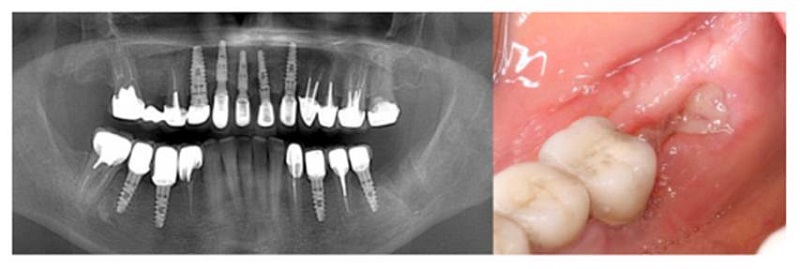

Una vez preparado el lecho quirúrgico, se colocó en la zona de intervención una mezcla de injerto de hueso tipo Lumina Bone Porous Lumina Coat con tetraciclina hasta alcanzar una mezcla uniforme. Luego, fueron tomados puntos con sutura reabsorbible. Se medicó a la paciente con acetaminofén de 325 mg + codeína de 30 mg durante 3 días; también amoxicilina de 500 mg, 3 veces al día durante 7 días. Finalmente, se programó a la paciente para una cita de control un mes después, donde se constató una adecuada cicatrización y remisión de molestias o dolor. Los controles a los 45 días y 3 meses posquirúrgicos permitieron comprobar una adecuada oseointegración, excelente capacidad retentiva y adaptabilidad ideal, tanto del injerto como del implante (figuras 3A y 3B).